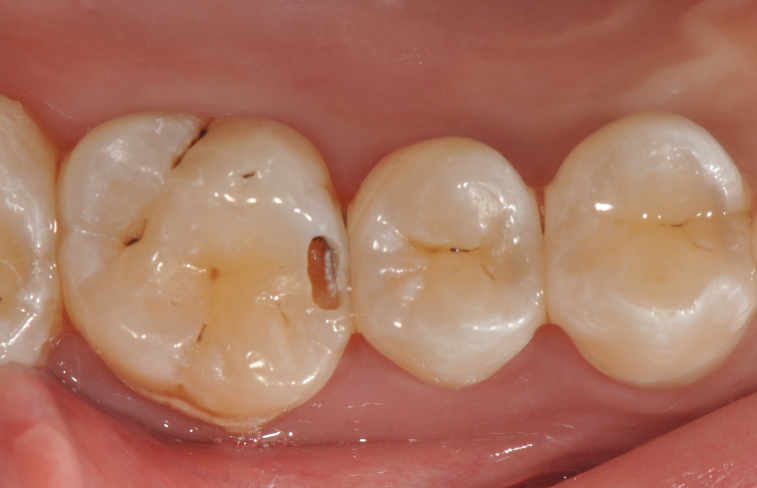

牙医-马小寒【实操病例】

右上6号牙位的近中,可见隐约龋坏